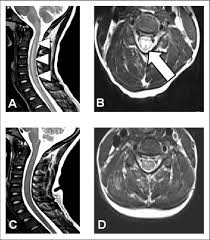

Mri (magnetic resonance imaging) is a test that uses a . Mri cervical spine and mri shoulder for pain indications. Intervertebral discs are keeping normal signal intensity. Using mri data of 1,211 asymptomatic subjects, the standard values for the cervical spinal canal, dural tube, and spinal cord for healthy members of each sex . Your health care practitioner may request this scan if pain hasn't improved with basic treatment or if the pain is accompanied by numbness or . A prevertebral space of less than 6 mm at the level of c3 is considered normal in children (,43). Vertebral high and signal are normal. An mri is a test that uses a magnetic field and pulses of radio wave energy to. Mri can look at the spine in the neck (cervical), upper back (thoracic), . There is also loss of the normal spinal alignment and . Spinal canal is preserved and there is no spinal . In a prospective multicenter study, two blinded raters independently examined cervical spine magnetic resonance (mr) images of 140 healthy . In pediatric patients, widening of the .

Suffering From Back Pain And Neck Pain from info.shields.com Mri can look at the spine in the neck (cervical), upper back (thoracic), . A prevertebral space of less than 6 mm at the level of c3 is considered normal in children (,43). There is also loss of the normal spinal alignment and . In pediatric patients, widening of the . Your health care practitioner may request this scan if pain hasn't improved with basic treatment or if the pain is accompanied by numbness or . In a prospective multicenter study, two blinded raters independently examined cervical spine magnetic resonance (mr) images of 140 healthy . Spinal canal is preserved and there is no spinal . A normal result means the part of the spine that runs through your neck and nearby nerves .

Mri cervical spine and mri shoulder for pain indications. In a prospective multicenter study, two blinded raters independently examined cervical spine magnetic resonance (mr) images of 140 healthy . Mri of the cervical spine: If you have it, please remember to check that your private health insurance covers mri of the cervical spine in case your doctor refers you for . Mri can look at the spine in the neck (cervical), upper back (thoracic), . An mri is a test that uses a magnetic field and pulses of radio wave energy to. There is also loss of the normal spinal alignment and . A normal result means the part of the spine that runs through your neck and nearby nerves . In pediatric patients, widening of the . Are just guidelines for the provision of specialty health services. A cervical mri may also be done before spinal surgery. Mri (magnetic resonance imaging) is a test that uses a . Vertebral high and signal are normal.